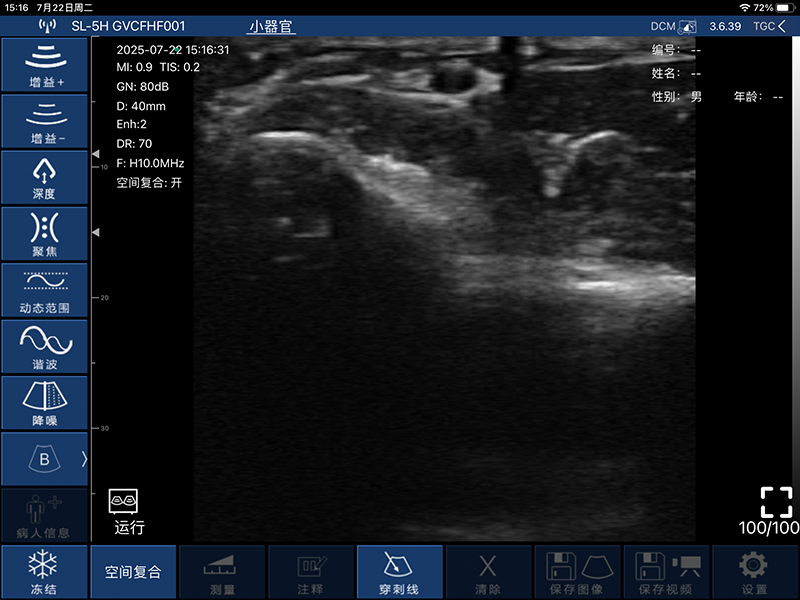

带指套探头的掌上彩超,小小的掌超主机放在口袋可随处走,手指套着探头即可完成打图成像,让手不再需要握着探头而可解放出来还能拿其他东西,特别适合术中等应用

- 图像调节:增益、焦点、反相脉冲谐波、降噪

- 穿刺辅助功能:平面内穿刺引导线功能,平面外穿刺引导与血管自动测量功能